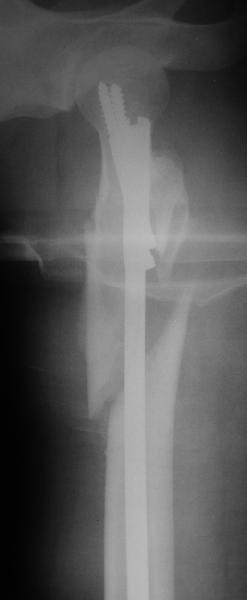

Фас

Оперировали вчера. Не сказать, что все прошло гладко - вертельная область была расколота и в сагиттальной, и во фронтальной плоскости, гвоздь попал в перелом и сместился кзади, что заметили уже после введения винтов, пришлось все извлечь и переставить. Снимки в приложении. Буду признателен за комментарии.

На этой же стороне у нее еще пятка сломана, так что раннюю нагрузку не предполагаем.